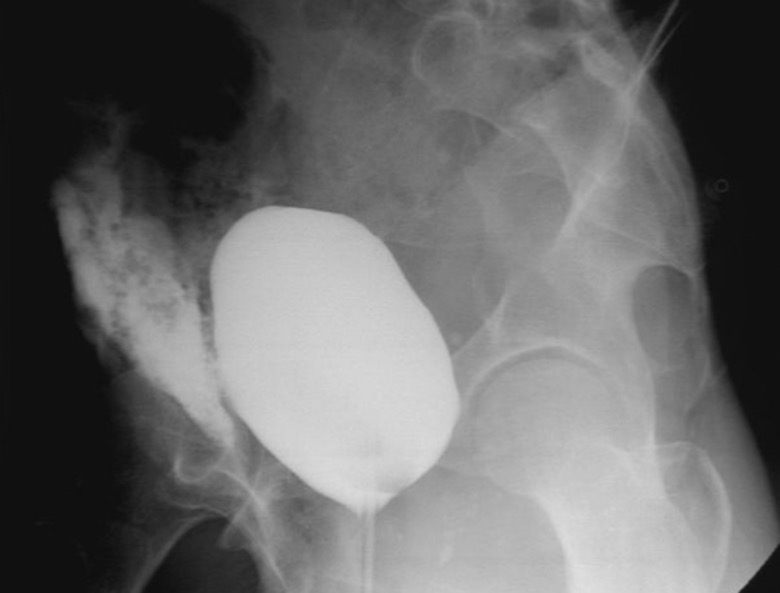

Figure1. Вид сбоку, демонстрирующий экстравазацию контраста перед мочевым пузырем.